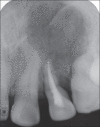

Palatogingival groove is an anatomical malformation that often causes severe periodontal defects. Treatments of such an anomaly present a clinical challenge to the operator. Careful endodontic and periodontal procedures may restore the form and function. In the present case; root canal therapy, apicectomy, and sealing of the groove with Biodentine™ were done. Bone graft was placed followed by platelet-rich fibrin (PRF) membrane. This treatment modality resulted in gain in attachment, reduction in pocket depth, and deposition of bone in the osseous defect. A 24 month follow-up is included.